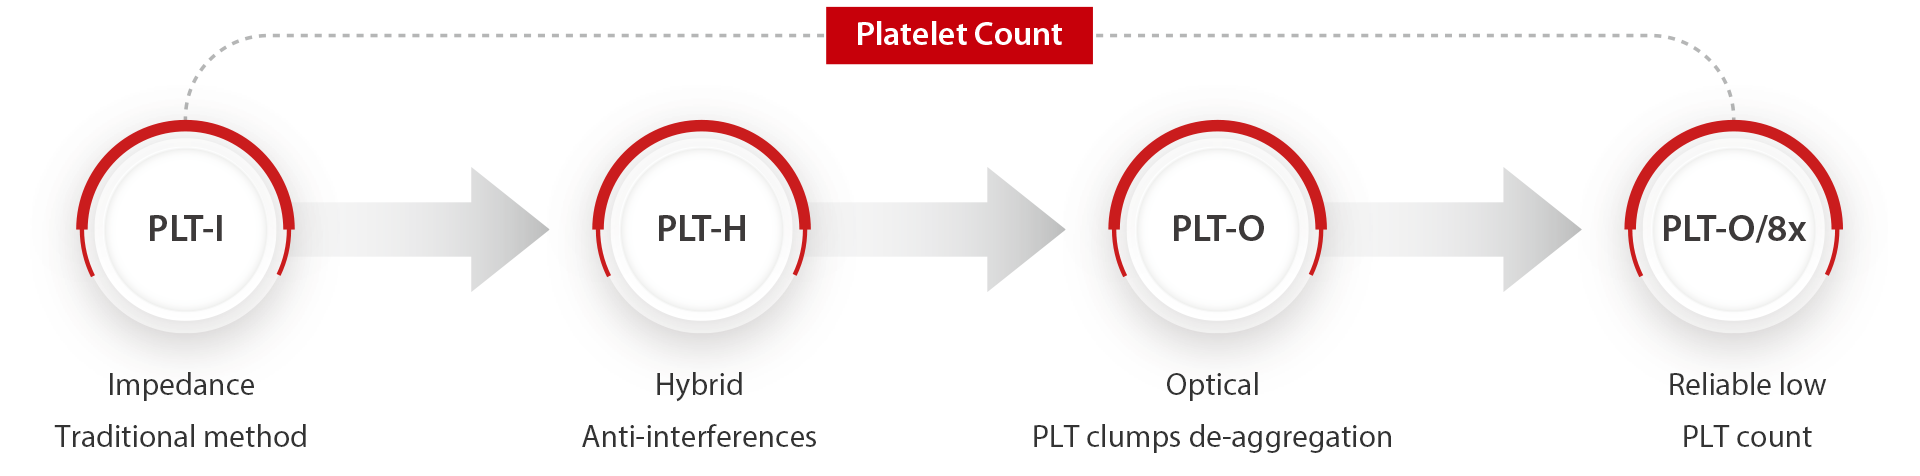

Comprehensive Solution for Accurate PLT Results

Brand new PLT-H in every CD test

PLT-O with Multiple Counting for Low-count Platelet

There is no need to re-aspirate samples. The instrument will automatically conduct 8 times statistical analysis on low PLT count samples to improve the detection accuracy.

Scattergram before and after Auto 8x PLT-O counting

PLT-O with automated PLT-clumps de-aggreation technology

It solves the problem of falsely low PLT count samples caused by EDTA induced pseudo-thrombocytopenia.

Automatic retraction and re-testing with PLT-O